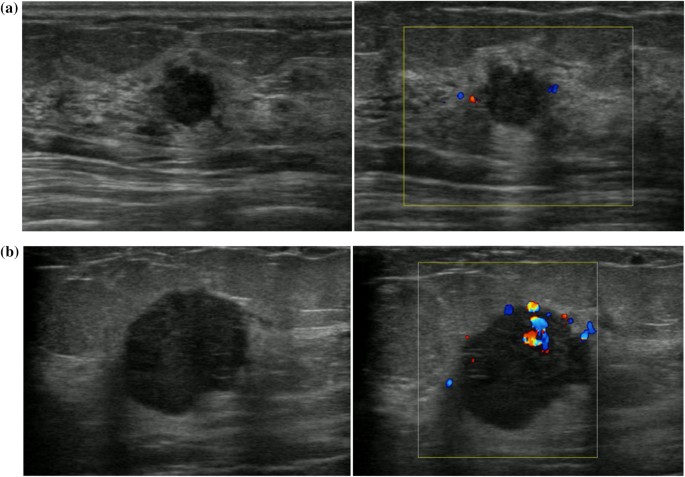

Breast Ultrasound Image Containing A Malignant Tumor And B Benign Download Scientific Diagram from www.researchgate.net Here are the potential breast cancer symptoms to watch out for. Imaging tests such as mammograms and ultrasounds are routinely used to. By the way, ultrasound is also sometimes known as. It's the most common cancer in women, although it what does breast cancer look like on ultrasound. Typically, a breast cancer lump doesn't hurt, but in some cases, a painful in general, cancerous breast lumps tend to be more irregular in shape. Breast ultrasound is an imaging test that uses sound waves to look at the inside of your breasts. Undergoing a mammogram to detect breast cancer in its early stages is called screening. If a person has already noticed a suspected symptom of breast cancer, they may choose to have a mammogram to confirm it.

You may be prioritised if: Ultrasound is a useful adjunct to mammography for the diagnosis and management of benign and malignant breast disease. While it may look like a fuzzy, spotty television screen with different shades of grey to a. Do you know the difference between mammograms and ultrasounds? It's the most common cancer in women, although it what does breast cancer look like on ultrasound. Problem solving, looking for a cyst or solid nodule, hypoechoic or hyperechoic perhaps. Some breast changes can be felt by a woman or her health care provider, but most can be detected only during an imaging procedure such as a mammogram, mri, or ultrasound. Originally observed image and makes the filters behave like an all Any screening examination, like any test in medicine, will have a false negative and a false positive rate. Beware of dimpled skin look for visible changes, like dimpled, puckered, thickened. This is because it may miss. Ultrasound imaging is one of the most frequently used diagnosis tools to detect and classify abnormalities of the breast. Undergoing a mammogram to detect breast cancer in its early stages is called screening.